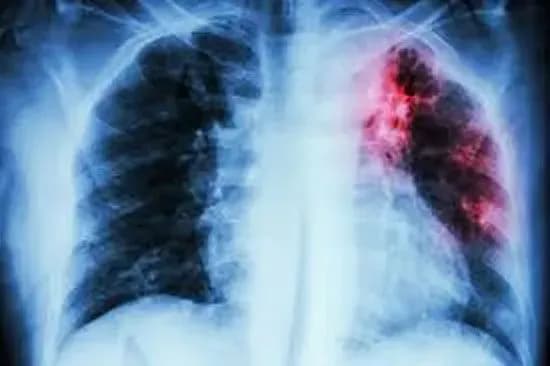

КИЇВ. 22 січня. УНН. В Україні, за даними з січня по вересень 2019 року, кількість хворих на всі форми активного туберкульозу віком до 14 років становить понад 400 осіб. Про це УНН повідомили у Центрі медичної статистики МОЗ України у відповідь на запит.

Так, за 9 місяців 2019 року, на обліку в закладах охорони здоров’я перебуває 446 осіб віком від 0-14 років, хворих на всі форми активного туберкульозу.

Додамо, що за відповідний період на обліку в закладах охорони здоров’я перебуває 31 615 хворих на всі форми активного туберкульозу.